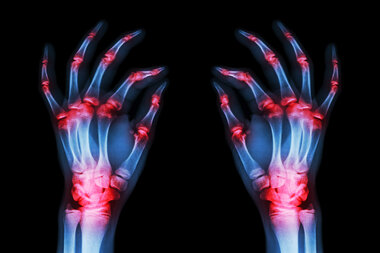

Rheumatoid arthritis (RA) is an autoimmune condition that causes pain and inflammation in the body’s joints. The immune system attacks the synovium (the lining of the joints), leading to inflammation, stiffness, swelling and pain that usually affect the hands, knees or ankles but can also cause issues with the eyes, heart, circulatory system and lungs.